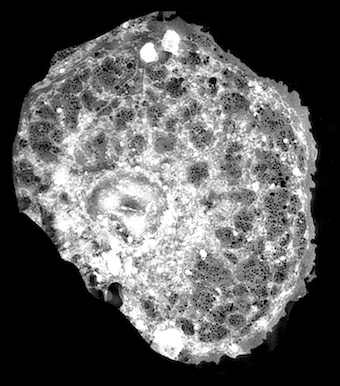

Recent studies of liver tissues from the Bielefeld group included the use of super-resolution direct stochastic optical reconstruction microscopy (dSTORM) to examine an important class of liver sinusoidal endothelial cells (LSECs), said to open a path to in vitro examination using highly resolving localization microscopy techniques that could be implemented on non-specialized fluorescence microscopes.

Another recent Bielefeld project studied LSECs through the complementary use of two different super-resolution optical microscopy modalities - 3D structured illumination microscopy (3D-SIM) and single molecule localization microscopy - in a common optical platform. This involved using 3D-SIM to acquire highly resolved overviews of large sample areas, before applying single molecule localization microscopy to selected locations of interest.